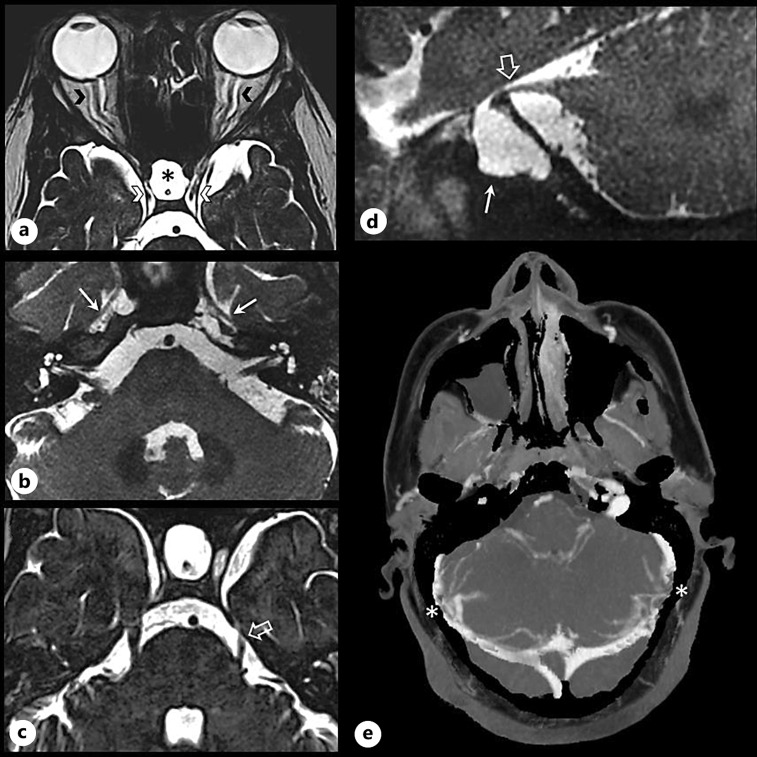

Case presentation: We reported herein another rare clinical feature of IIH: trigeminal neuralgia in association with meningocele. This 35-year-old obese woman initially presented with chronic headaches and papilledema. Cerebral MRI showed classical IIH findings. The CSF opening pressure was increased. A treatment coupling acetazolamide and iterative lumbar punctures led to the regression of papilledema, but headaches were difficult to control. Ten years later, while she was lost to follow up and treated with acetazolamide by her general practitioner, she developed extremely painful neuropathic pain in the left trigeminal nerve territory, in association with a recurrence of the chronic headaches. A new MRI showed new bilateral cavum trigeminal meningoceles, predominantly on the left side, associated with an atrophy of the cisternal segment of the left trigeminal nerve. Angio-CT showed transverse sinus stenosis, treated by stenting. After this treatment, IIH symptoms disappeared, while trigeminal neuralgia amplified: a surgical procedure led to its complete disappearance.